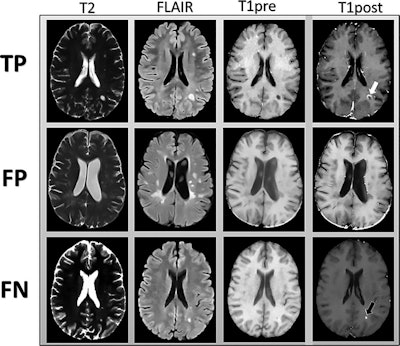

Patients with MS are likely to undergo repeated, periodic MRI scans with a GBCA to evaluate hyperintense lesions. Clinicians target active lesions with T2-weighted, proton density-weighted, and fluid-attenuated inversion-recovery (FLAIR) imaging sequences because accurate characterization of lesions is critical for effective patient treatment. Gadolinium, however, is a cause for concern among clinicians due to the element's association with nephrogenic systemic fibrosis and evidence of gadolinium deposition in various tissues and bone long after GBCA-enhanced scans.

The researchers trained a convolutional neural network to classify enhanced lesions on unenhanced 2D MRI slices for possible contrast enhancement in each slice. They then employed a connected network to combine the slice scores to accurately predict results.

Their deep-learning approach achieved a sensitivity of 78% (± 4%) and specificity of 73% (± 2.7) averaged across the five test sets for predicting contrast enhancement in each MRI slice. In addition, sensitivity was 72% (± 9%) and specificity was 70% (± 6%) in determining the presence of any enhancing lesions in an MS patient.